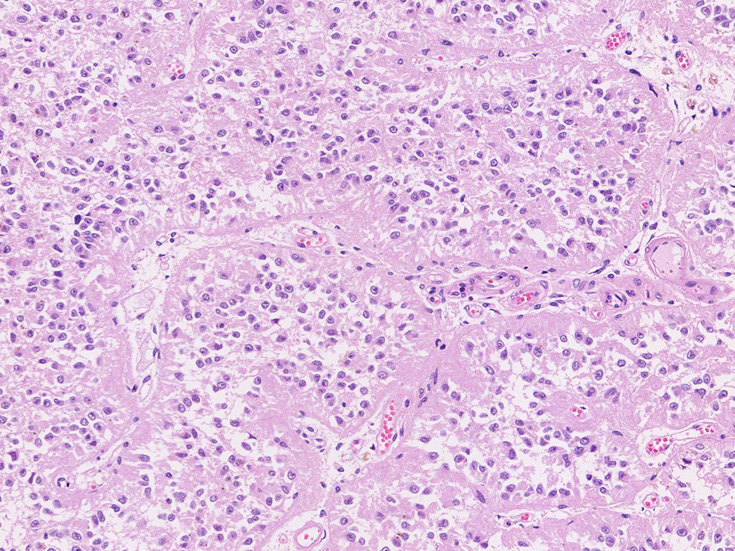

松果体の組織像

normal pineal gland tissue